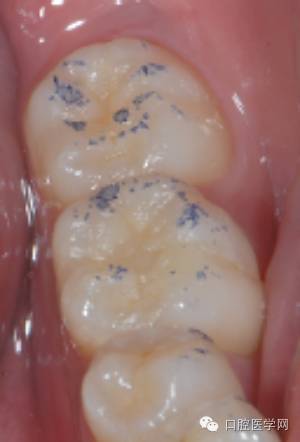

印章覆盖成形

要点:

1、若龋洞较深,分层充填,在最后的一层树脂固化前覆盖印章

2、 若龋洞较浅,可单层充填

3 、树脂不宜过多,否则影响形态恢复的准确性,并为调牙合带来困难,影响充填效果

初步完成

检查咬合